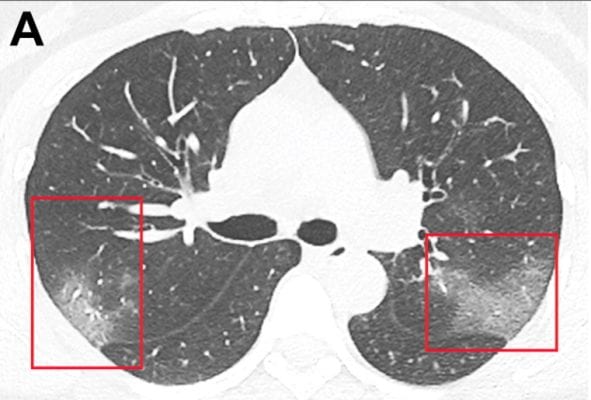

ჩინეთში, ადგილობრივმა მედიკოსებმა კორონავირუსით დაავადებული ადამიანის ფილტვების ამსახველი ფოტოები გაასაჯაროვეს, რომელიც 33 წლის ქალბატონს ეკუთვნის. დაინფიცირებულ ადამიანზე ჩატარებული ტომოგრაფიის მერე, ასეთი სურათი გამოიკვეთა.

A ფოტოზე ნაჩვენებია ფილტვების მდგომარეობა, როდესაც პაციენტს კორონავირუსი დაუდგინდა. ამ დროს 33 წლის ქალბატონს მაღალი ტემპერატურა და ფილტვების შეშუპება აღენიშნებოდა.